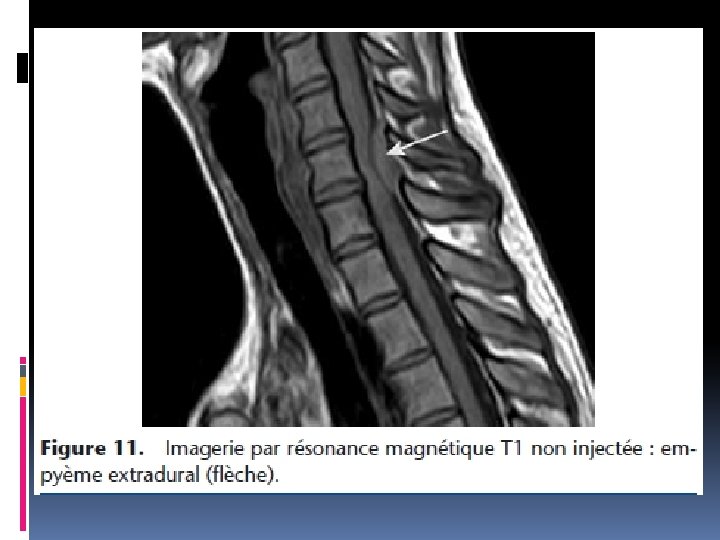

IV. Bilan paraclinique Tout tableau de compression médullaire franche et/ou d’aggravation rapide impose la réalisation d’une IRM panmédullaire en urgence Visualise les lésions épidurales, osseuses, le siège de la compression, son extension, lésions asymptomatiques à d’autres niveaux

VI. Etiologies a-Compression médullaire aigue: Trauma du rachis direct ou indirect ( AVP; chutes; …. ) b-compression médullaire chronique ou lente b-1: Causes extra-médullaires Causes rachidiennes: tumeurs vertébrales bénignes ou malignes (primitives ou secondaires) Causes intrarachidiennes: -extradurales: tumeurs épidurales malignes ; lipome -intradurales: neurinomes, méningiomes, autres tumeurs , processus non tumoraux dont abcès, parasitose , tuberculome b-1: Causes intra-médullaires Tumeurs: épendymome, gliome, angiome médullaire Infections: abcès, tuberculome, parasitose, syphilis